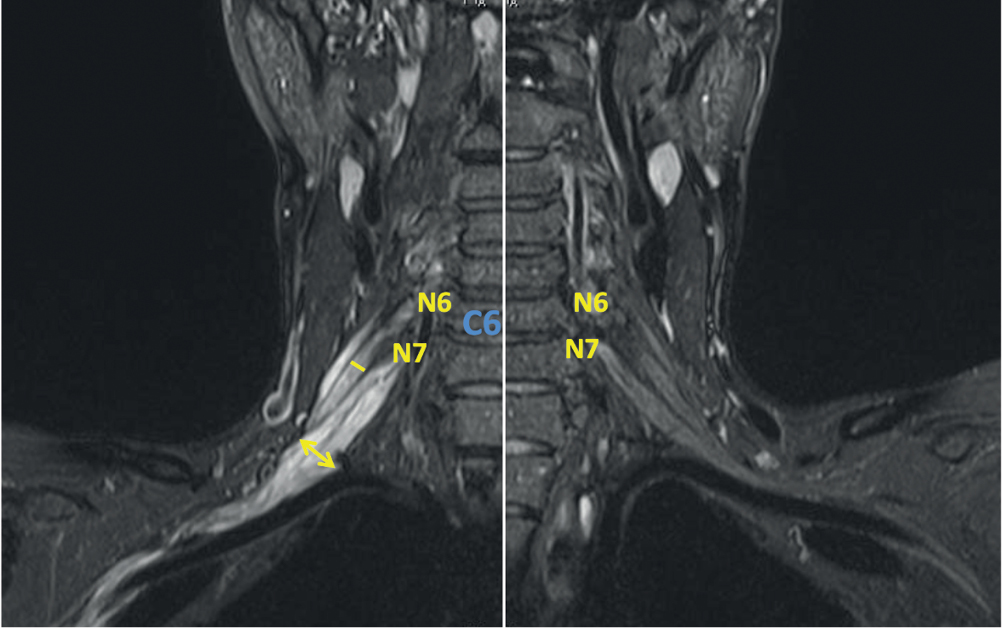

Рис. 6. МРТ ПС пациента с мХВДП (катамнез 6 лет, исследование выполнено на фоне терапии глюкокортикостероидами в течение 2 лет). Отмечается повышение МР-сигнала в режиме STIR на всем видимом уровне с двух сторон без утолщения стволов ПС.

Fig. 6. MRI of BPs in a MADSAM patient (6-year follow-up history; assessed during 2-year glucocorticosteroid therapy). Hyperintense STIR MRI signal bilaterally at the entire visible level without any thickened BP trunks.